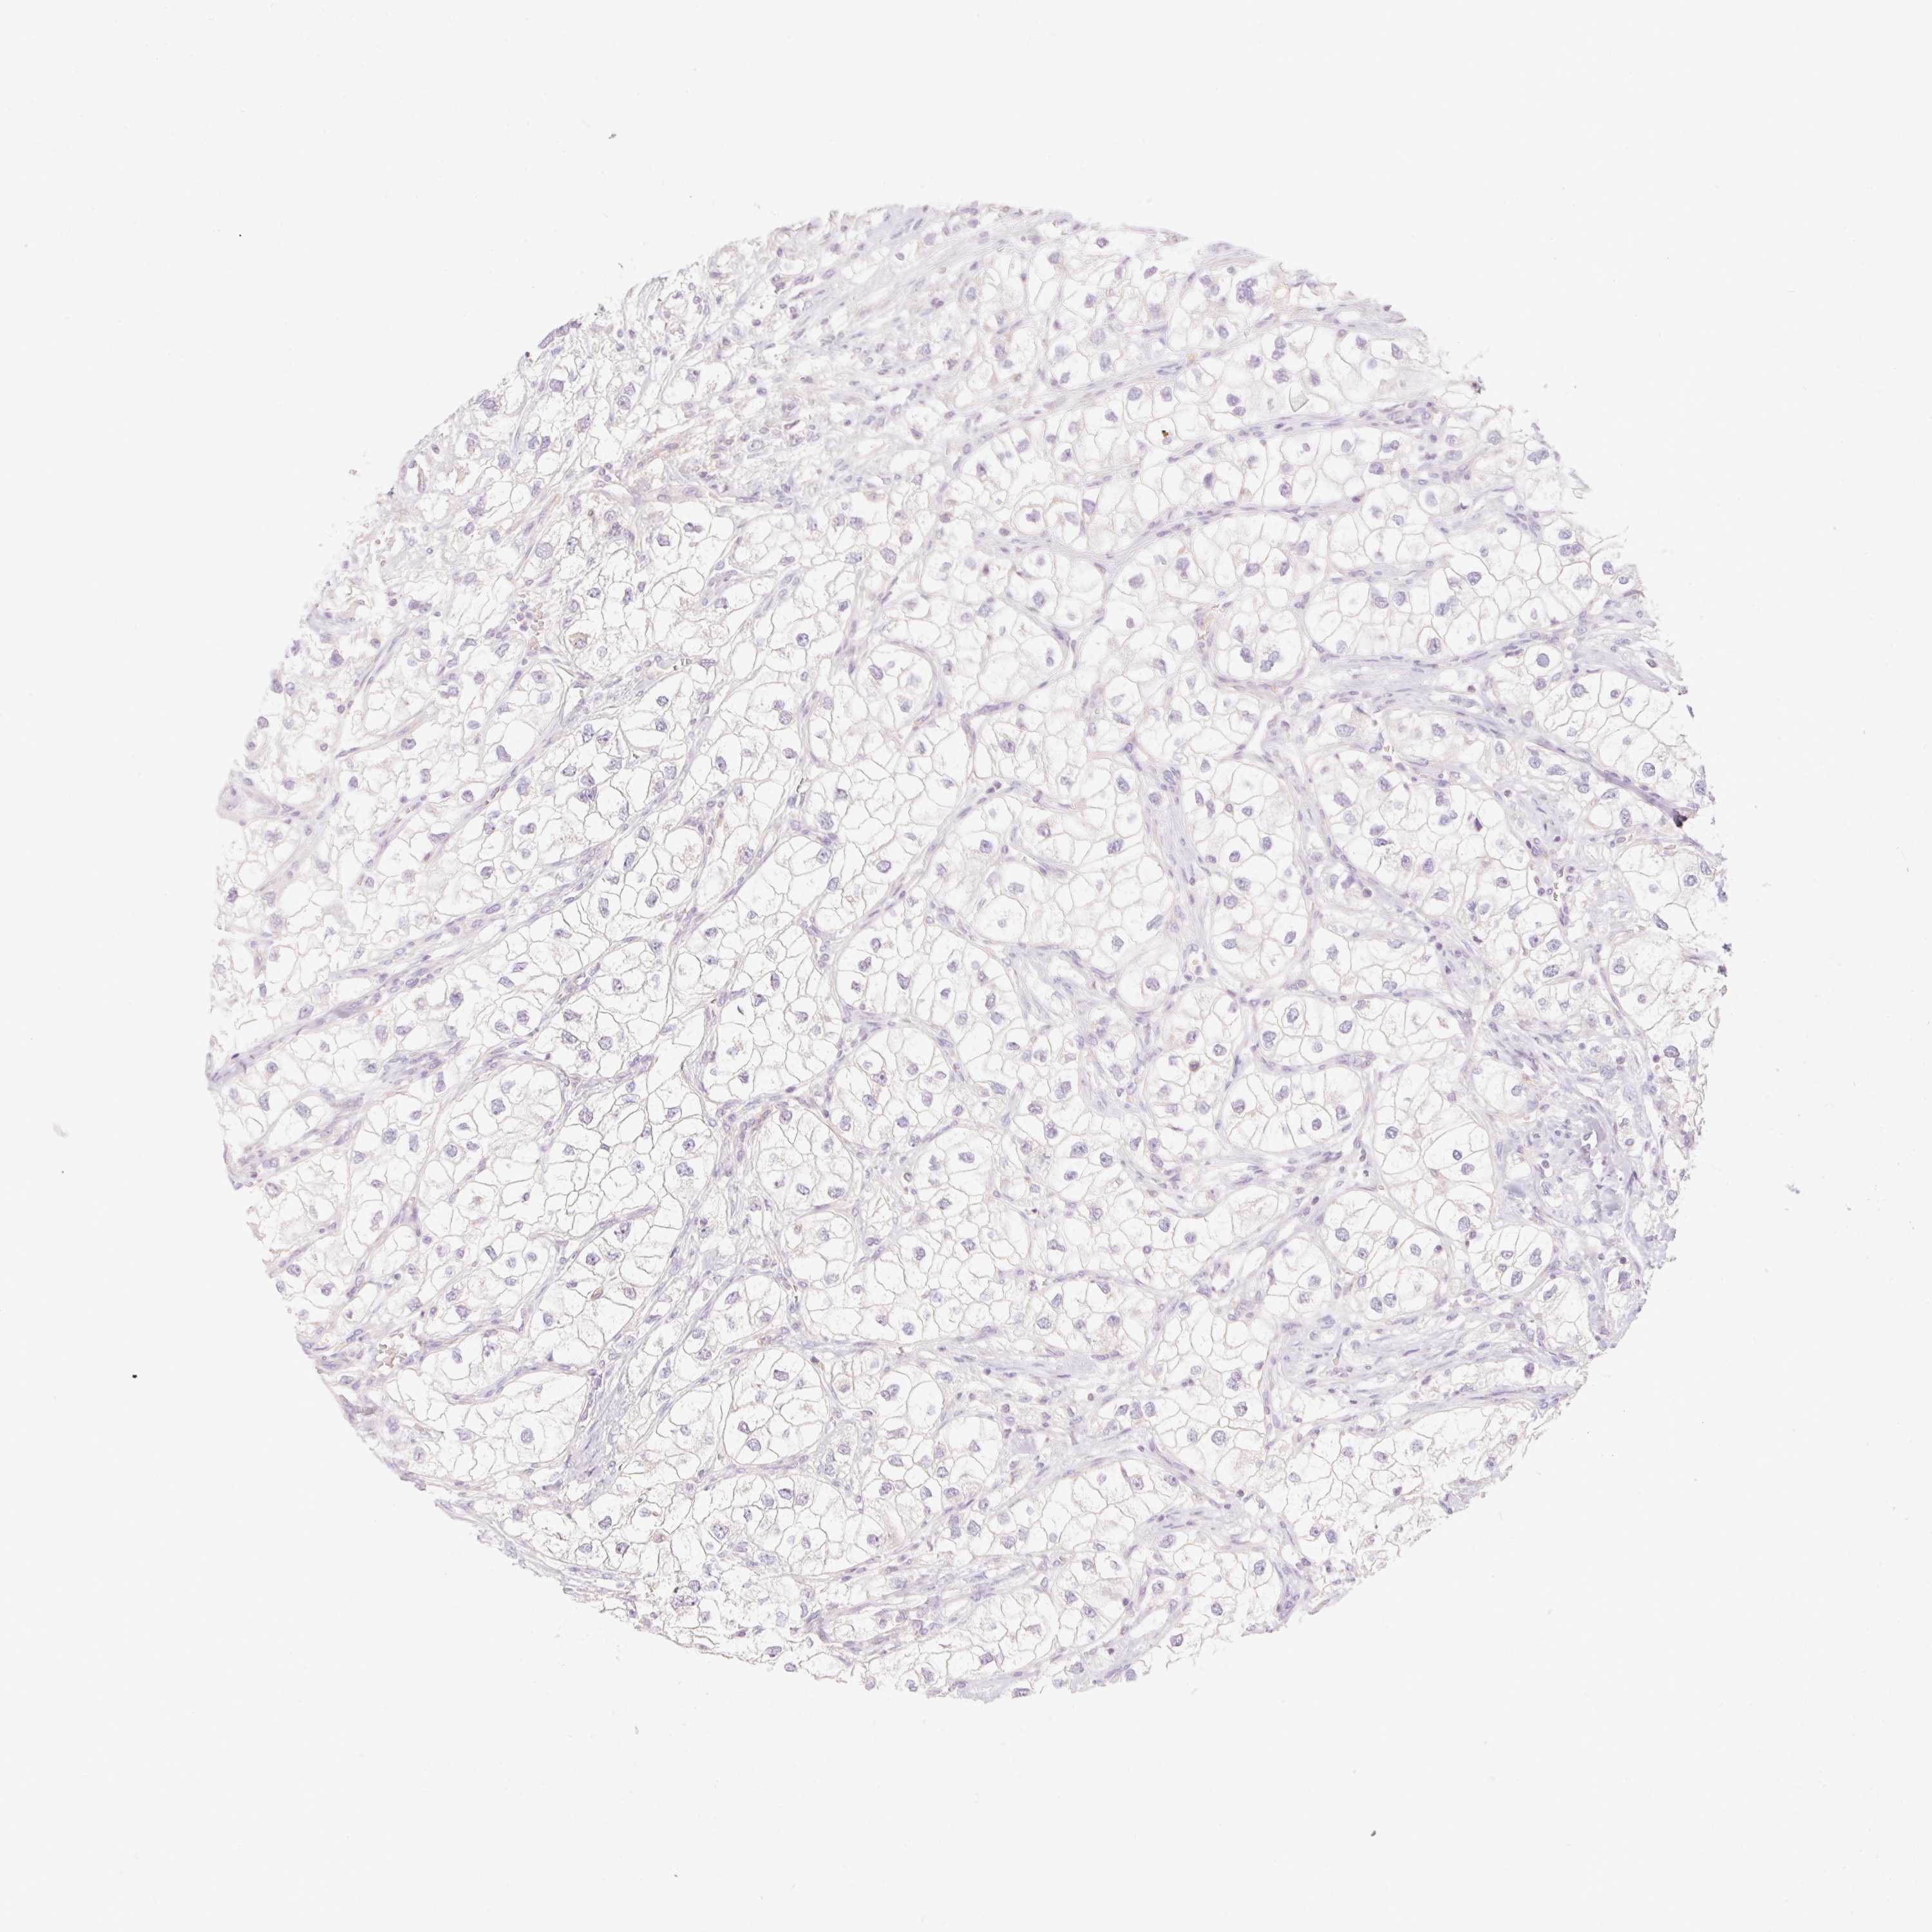

KIDNEY RENAL PAPILLARY CELL CARCINOMA (TCGA) - Interactive survival scatter ploti

The Survival Scatter plot shows the clinical status (i.e. dead or alive) for all individuals in the patient cohort, based on the same data that underlies the corresponding Kaplan-Meier plots. Patients that are alive at last time for follow-up are shown in blue and patients who have died during the study are shown in red.

The x-axis shows the expression levels (FPKM) of the investigated gene in the tumor tissue at the time of diagnosis. The y-axis shows the follow-up time after diagnosis (years). Both axes are complimented with kernel density curves demonstrating the data density over the axes. The top density plot shows the expression levels (FPKM) distribution among dead (red) and alive patients (blue). The right density plot shows the data density of the survived years of dead patients with high and low expression levels respectively, stratified using the cutoff indicated by the vertical dashed line through the Survival Scatter plot. This cutoff is automatically defined based on the FPKM cutoff that minimizes the p-score. The cutoff can be changed by dragging the vertical line or by entering a cutoff value in the square labeled "Current cut-off".

Under the Survival Scatter plot the p-score landscape (black curve; left axis) is shown together with dead median separation (red curve; right axis). Dead median separation is the difference in median mRNA expression between patients who have died with high and low expression, respectively. It is calculated as follows: median FPKM expression of dead patients with high expression - median FPKM expression of dead patients with low expression. This is intended to aid the user in visually exploring custom cutoffs and the associated p-scores and dead median separation.

Individual patient data is displayed and can be filtered by clicking on one or more of the category buttons on the top of the page. Categories describing expression level and patient information include: high, low, alive, dead, female, male and tumor stages. The scale of the x-axis can be toggled between linear and log-scale by clicking on the "x log" button. Mouse-over function shows TCGA ID, patient information and mRNA expression (FPKM) for each patient.

& Survival analysisi

Kaplan-Meier plots summarize results from analysis of correlation between mRNA expression level and patient survival. Patients were divided based on level of expression into one of the two groups "low" (under cut off) or "high" (over cut off). X-axis shows time for survival (years) and y-axis shows the probability of survival, where 1.0 corresponds to 100 percent.

MYO1D is not prognostic in Kidney Renal Papillary Cell Carcinoma (TCGA)